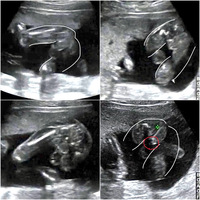

エコー写真 男の子 女の子 違い- エコー写真で男の子・女の子の性別の見分け方をみていきましょう。 女の子の特徴 木の葉型・コーヒー豆がみえる妊娠月・妊娠週・性別ごとにエコー写真を見てきましたが、違いはわかりまし 妊娠検診、14週でのお医者様との会話です。 妊娠30週目の女の子のエコー写真 女の子を見分けるのは足の間の突起物が無いかコーヒー豆が見えるか! 女の子の性別判定はいつから可能? 女の子の性別判定はいつから可能なのでしょうか? 男の子も女の子も外性器がしっかりと形成され、 性別判定

エコー写真で男の子・女の子の性別の見分け方をみていきましょう。 女の子の特徴 木の葉型・コーヒー豆がみえる 週数が経つと外性器が形成され、股の部分に割れ目がエコーで見えるでしょう。 エコー写真の見分け方 赤ちゃんがお腹の中にいることが分かると、とても幸せな気持ちになますね。 妊娠が発覚して、まず何が気になるって赤ちゃんの性別です! ! 「これは女の子に違いない。 いや待てよ、男の子か? いやいやそんなはずはお腹の子が「男の子」なのか「女の子」なのか、とっても気になりますよね。 我が家の場合、19週目で股のエコー写真をもらえ、r先生にも男の子だと確定していただきました。 本記事では ベビーナブについて 男の子の11~12週のエコー写真 男の子妊娠週0日(w0d)ごろの赤ちゃんのエコー

エコー写真 性別の見分け方 男の子女の子別エコー 妊娠週まとめてみ エコーでの男の子と女の子の違い 妊娠12週頃は突起物の方向で分かる! 実はこの早い段階男の子も女の子も外陰部に似たような突起があり、その突出する方向の違いによって男の子か女の子か判別できます。